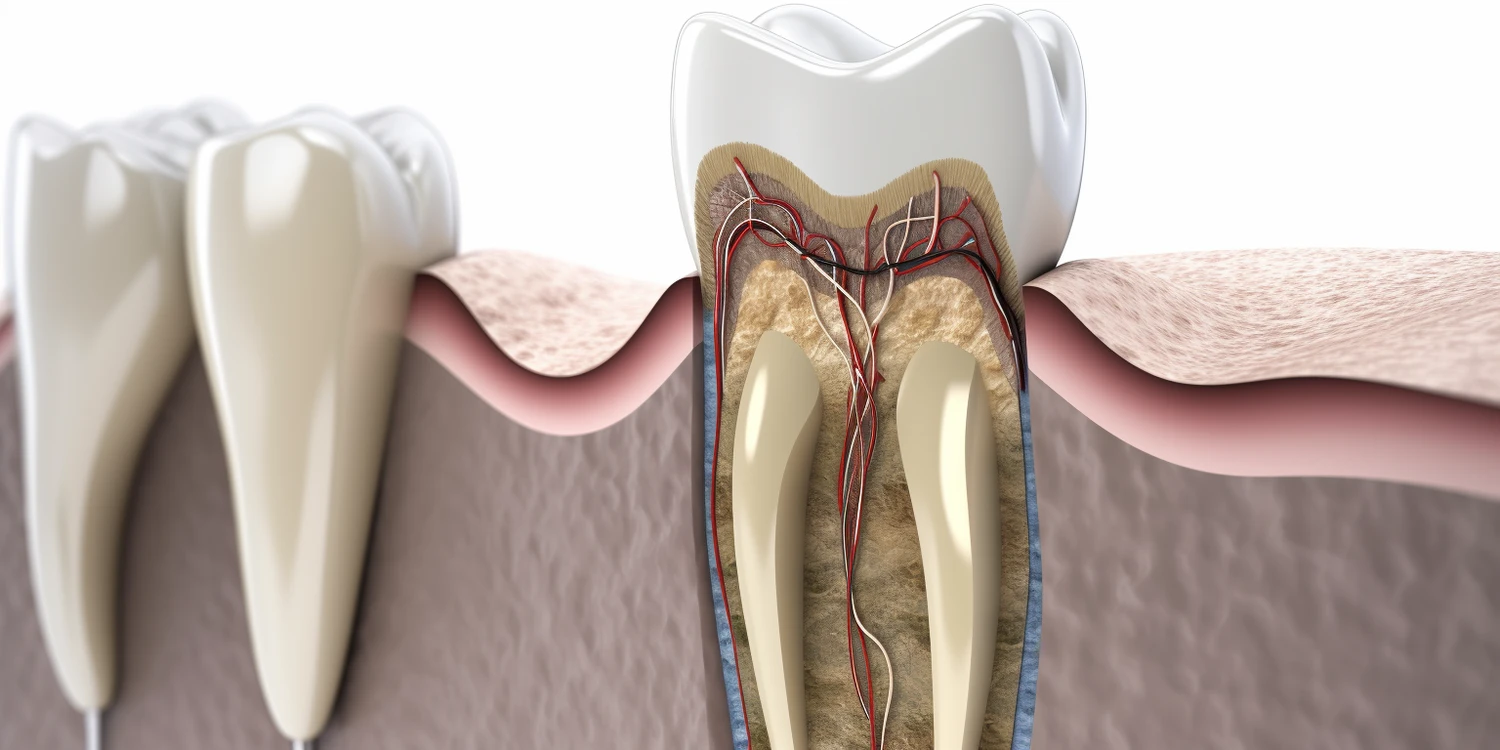

Leczenie kanałowe, znane również jako endodoncja, jest procedurą stomatologiczną, która ma na celu usunięcie zakażonej lub uszkodzonej miazgi zęba. Wiele osób obawia się tego zabiegu, zastanawiając się, czy leczenie kanałowe boli z znieczuleniem. Warto zaznaczyć, że znieczulenie miejscowe jest standardową praktyką w trakcie tego rodzaju zabiegów. Dzięki niemu pacjent nie odczuwa bólu w trakcie usuwania miazgi oraz późniejszych etapów leczenia. W przypadku niektórych pacjentów mogą wystąpić pewne dyskomforty związane z samym procesem, ale zazwyczaj są one minimalne i szybko ustępują po zakończeniu zabiegu. Warto również dodać, że doświadczenia pacjentów mogą się różnić w zależności od indywidualnej tolerancji na ból oraz stanu zdrowia zęba przed rozpoczęciem leczenia.

Proces leczenia kanałowego składa się z kilku kluczowych etapów, które mają na celu skuteczne usunięcie zakażonej miazgi oraz zabezpieczenie zęba przed dalszymi problemami zdrowotnymi. Pierwszym krokiem jest przeprowadzenie szczegółowej diagnozy przez stomatologa, który ocenia stan zęba i decyduje o konieczności wykonania zabiegu. Następnie pacjent otrzymuje znieczulenie miejscowe w celu zapewnienia komfortu podczas całej procedury. Po osiągnięciu odpowiedniego efektu znieczulającego dentysta przystępuje do otwarcia komory miazgi w celu dostępu do zakażonej tkanki. Kolejnym krokiem jest usunięcie chorej miazgi przy użyciu specjalistycznych narzędzi endodontycznych oraz dokładne oczyszczenie wnętrza kanałów korzeniowych. Po tym etapie stomatolog dezynfekuje wnętrze kanałów i wypełnia je materiałem biokompatybilnym, co zapobiega ponownemu zakażeniu. Na koniec lekarz zabezpiecza otwór w koronie zęba tymczasową lub stałą plombą oraz omawia dalsze kroki związane z ewentualną odbudową korony.